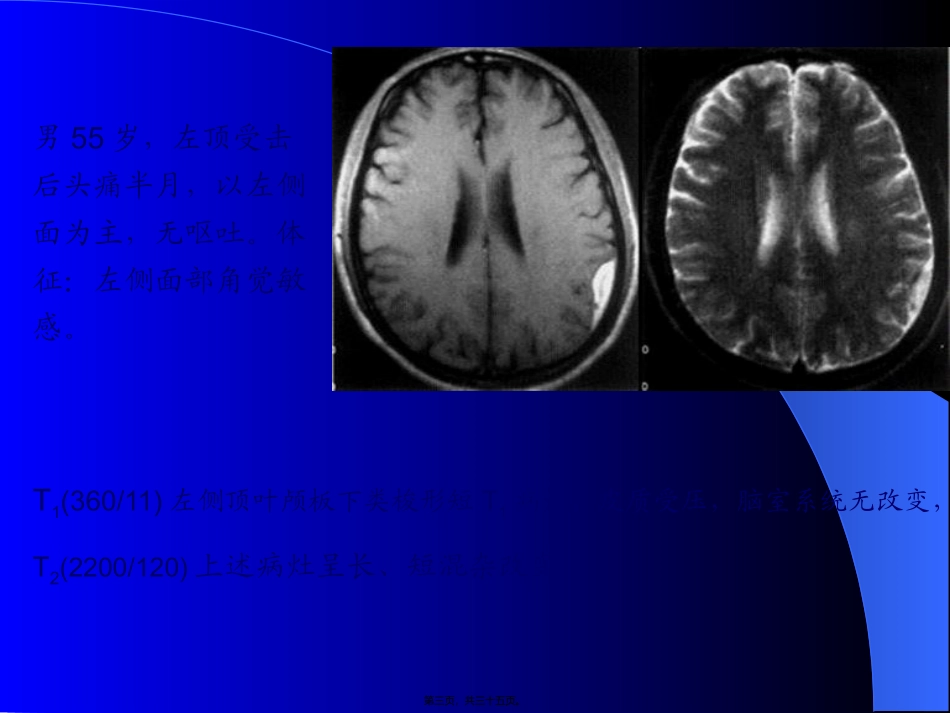

延髓颈髓蛛网膜下腔左侧椎动脉硬膜外脂肪第一页,共三十五页。女39岁,双上肢麻木,肉跳手变细2年。双上肢肌萎缩,肌力III-IV,颈5以下痛觉减低。T1小脑扁桃体及延髓下疝至颈椎管内颈3-胸4脊髓中央管扩张;FLASH(500/45/35)枕大池颅内外段消失,延髓中央管闭塞,颈1-2后纵韧带增厚钙化第二页,共三十五页。男55岁,左顶受击后头痛半月,以左侧面为主,无呕吐。体征:左侧面部角觉敏感。T1(360/11)左侧顶叶颅板下类梭形短T1病灶,皮质受压,脑室系统无改变,T2(2200/120)上述病灶呈长、短混杂改变。第三页,共三十五页。男59岁,急起双下肢无力三天,1月前有轻微头部外伤史。伸舌偏右,双下肢肌力IV,左侧上肢张力增高,左侧巴氏征(+)。T1(360/11)两侧额叶脑外大片长梭形短T1病灶,局部皮质受压,大脑纵短T1病灶;T2(2200/120)上述病灶呈长T2及混杂T2改变;T1(320/15)上述病灶呈短T1,两侧脑室、前角受压,变形,下移。第四页,共三十五页。女58岁,反复头痛伴双眼视力下降1年,左肢体无力三天。左侧中枢性面瘫,左上肢肌力III-IV。(1,2)T1(360/11)右侧额叶顶见大片低信号,脑组织介面不清;(3,4)T2(3300/120)上述病灶呈长T2信号;(5,6)增强T1(320/15)上述病灶呈不规那么脑回样、片状强化。第五页,共三十五页。男43岁,急起右侧肢体无力,言语不清1小时。神志清,右侧肢体肌力IV。(1,2)T1(360/11)左侧额顶颞叶顶见大片稍长T1信号,其间有小块状T1改变,占位效应显著,右侧脑室体旁小点状长T1信号;(3,4)T2(2200/120)上述病灶呈长T2信号,累及皮层。第六页,共三十五页。男58岁,急性头痛,言语不清2天。1年来反复发作;失语,伸舌偏右,右半身肌力差。(1,2)T1左颞枕叶大片长T1信号,左侧基底节点状长T1信号;信号;(3,4,5)T2像上述病灶呈长T2信号;诊断:左颞枕叶脑堵塞(陈旧性);左侧基底区腔隙性脑堵塞(病灶新)。第八页,共三十五页。男57岁,急起右侧肢体乏力伴意识不清12天。睁眼昏迷,右侧肢体肌力0。(1)T1左侧大脑半球有大片长T1信号,其中可见斑点状短T1信号,左侧面脑室轻度受压;(2)T2像上述病灶呈混杂T2信号;由于位于左大脑动脉分布区,堵塞后出血多为瘀斑状,无血肿中心,含铁血黄素沉着呈不规那么的点状。第九页,共三十五页。女69岁,渐起发呆半月,3天前言语不清、吞咽困难。神志欠清,右侧上下肢肌力差,病理反射(+)。(1,2)T1左侧颞叶有斑点状短T1信号及右侧基底区境界不清的稍长T1信号;(2)T2像上述病灶呈长T2信号;第十页,共三十五页。(1)T1右侧外囊区有一环状短T1信号,中心呈等T1,外周有稍长T1信号,占位性明显;(2)T2像上述病灶呈长T2信号,中心呈等T2,外周有水肿;(3,4,5)增强,血肿呈环状强化。男32岁,急起头痛,口角歪斜,左侧肢体无力2天。伸舌偏右,左侧肢体肌力IV。第十一页,共三十五页。女69岁,渐起发呆半月,3天前言语不清、吞咽困难。神志欠清,右侧上下肢肌力差,病理反射(+)。(1,2)T1左侧颞叶有斑点状短T1信号及右侧基底区境界不清的稍长T1信号;(2)T2像上述病灶呈长T2信号;第十二页,共三十五页。男24岁,头晕伴视物成双1周余。(1)脑干片状高信号,界清,脑干不膨大,第四脑室顶受压;(2)T2像上述病灶呈长T2信号;(3,4)增扫病灶周边强化。第十三页,共三十五页。女30岁,阵发性四肢抽搐7天,有脑血管病史,神清,神经系统(-)。(1)左侧额后片状水样长T1信号,边缘小结节改变及条状短T1信号;(2)T2像上述病灶呈长T2信号,其中有块状短T2信号,有弧形流空现象,占位性不明显;(3,4)增扫结节状病变呈团块化显著强化,左侧脑室轻微扩大。第十四页,共三十五页。男52岁,间歇性头晕10年,抽搐1次,神经系统(-)。(1)右侧枕叶呈斑片状短T1信号信蜂窝状长T1信号,并可见迂曲的流入增强信号,局部脑沟增宽。无水肿及占位;(2)T2像上述病灶呈长。T2信号,流空明显,并可见增粗的右侧大脑中动脉的分支向病灶供血;(3,4)增扫病灶呈片状、扭曲条状强化。第十五页,共三十五页。女72岁,头昏、左侧肢体无力3月,神经系统(-)。(1)右侧鞍旁囊性短T1信号,内有少许等T1信号,境界清楚;(2)病灶呈环状低信号,其中心为小圆形长T2高信号;(3-4)增扫呈...